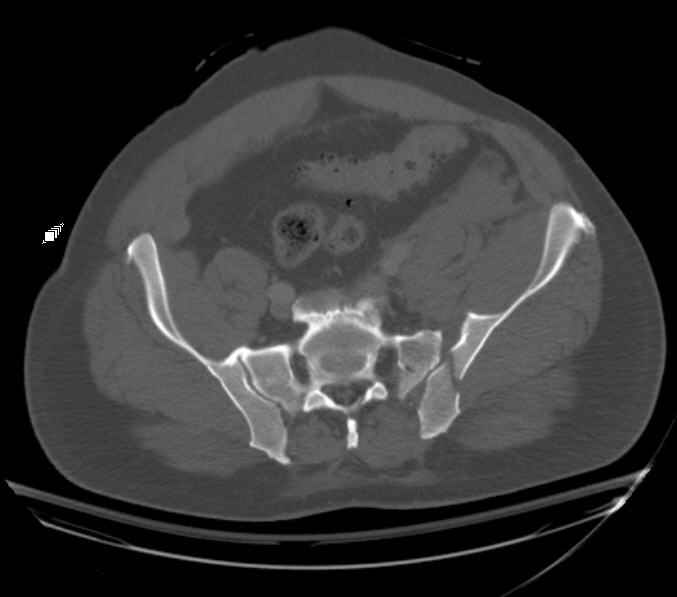

Hello gentlemen- Case is 52 YO male, fell out of treestand while deerhunting. He is 6 ft, approx. 260-275 lbs. Was hemodynamic unstable at local ER, sent to our Trauma center where circumferential pelvic binder placed and pt. stabilized with fluid, blood, and rewarming. Angiography not performed. An extraperitoneal bladder disruption was found, uro elected to treat non-operatively. Initial xray (not shown) demonstrated 5-7 cm wide at symphysis and SI joint. The first image attached is of CT once binder is in place. On post trauma day 5 the pt was taken to OR for ORIF of his iliac wing fracture and SI dislocation. The swelling/3rd spacing of fluid in the area of symphysis was profound, but quite acceptable posteriorly. Patient was prone for procedure, as I thought too difficult to fix the wing in lateral position. Of course the repair of wing was easy, but reduction of SI very demanding. The Floro images document the residual lack of reduction. That was the closest I could get it using 6mm joystick in wing, and clamp on sacrum and clamp through notch. The fixation was (initially) rigid. Anterior ex fix with supra-acetabular pins was placed due to condition of soft tissues, massive "beer-belly" overhanging the crest. Post trauma day ten patient's xray shows failure of posterior construct. Plan was to perform revision orif once soft tissues resolve considerably for full anrterior fixation and posterior fixation. However, while Im away for holiday (on Post trauma day 15), pt is developing septic clinical appearance, and trauma suspects pelvic abcess near symphysis and performs I and D - finds nothing but no primary closure performed. Posterior tissues/incision continue to look healthy. Now is post trauma day 17, pt is still tubed/on dopamine/and wbc still elevated, anterior incision still packed open. Clearly must get to bottom of possible sepsis, but then what? Thanks for you time - sorry for such lengthy clinical description. Thomas Schaller Kalamazoo, Michigan

On 11/29 took patient back to OR and explored both his anterior and posterior wounds, removed loose illiosacral screws. Left behind the screws fixing illiac crescent. Found anterior wound clean and closed it. Found posterior wound with moderate seroma and some adjacent fat necrosis. Thus far, cultures negative, but not kidding myself on that fact. Wound VAC placed and going back tomorrow to reexamine wound and may close it or re-VAC one more time. Fixator remains in place.

My plan to revise fixation is in line with your suggestion - plate symphysis and anterior approach to SI joint. It appears from post - failure CT scan that the path of the more cephalad IS screw may be helpful to place a longer screw to engage opposite illiac wing as an option, or just anterior SI plates. not likely to do this tomorrow as he remains in a fragile clinical situation regarding his pulmonary status, and profound edema/induration around his pelvis/abdomen and thighs.